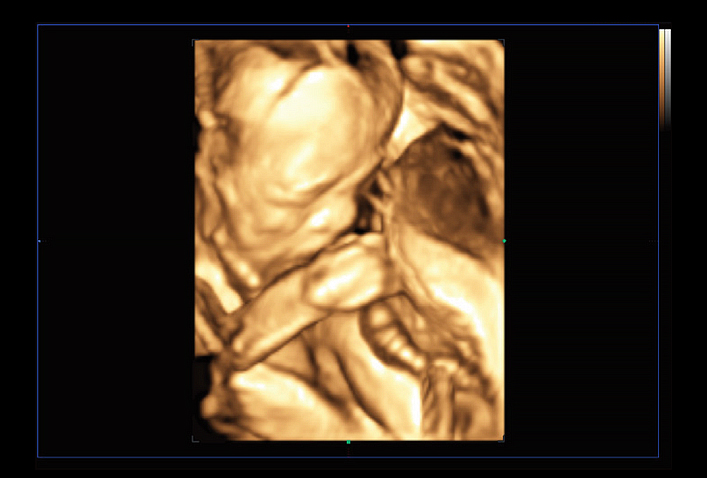

RealisticVue™ displays high resolution 3D anatomy with exceptional detail and realistic depth perception. User selectable light source direction creates intricately graduated shadows for better defined anatomical structures.